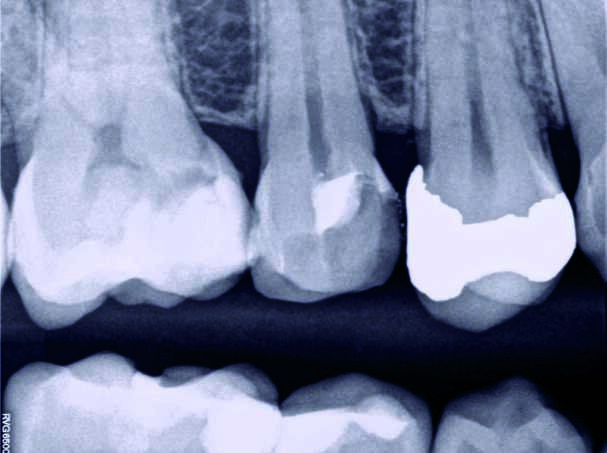

Ein 35-jähriger Patient kam mit vorübergehenden, provozierten Zahnschmerzen an Zahn #4 in die Zahnklinik. Die Diagnose lautete reversible Pulpitis. Es wurde dasselbe Behandlungsprotokoll zum Erhalt der Pulpenvitalität wie im klinischen Fall 1 eingehalten (Abb. 10, 11 und 12), nur dass in diesem Fall die endgültige Zahnreparatur nicht während derselben Sitzung erfolgte. Stattdessen wurde ein vorübergehendes strahlendurchlässiges Reparaturmaterial eingesetzt. Damit konnte die richtige Dicke des Materials für die Pulpa-Überkappung und seine korrekte Positionierung auf der Höhe des Lochs gewährleistet werden, während der Zahnrand für ein gutes Klebeprotokoll sauber gehalten wurde (Abb. 13, 14 und 15). Es wurde berichtet, dass die Erfolgsrate bei den Behandlungsverfahren zum Erhalt der Pulpenvitalität abfallen kann, wenn die endgültige Zahnreparatur zwei Tage nach dem ursprünglichen Verfahren durchgeführt wird. (8) Das MAP-System ist äußerst hilfreich im Hinblick auf eine präzise und stabile Platzierung des Überkappungsmaterials bei unmittelbaren und mittelbaren Verfahren sowie bei partiellen und vollständigen Pulpotomien. In diesem Fall erfolgte die abschliessende Reparatur 15 Tage nach dem ursprünglichen Verfahren und der Patient war vollständig symptomfrei. Neun Monate später wurde die vollständige Bildung des Kalkgewebes auf der Höhe der Pulpen-Überkappung festgestellt, der Zahn ist vital geblieben und der Patient ist vollständig symptomfrei (Abb. 16).